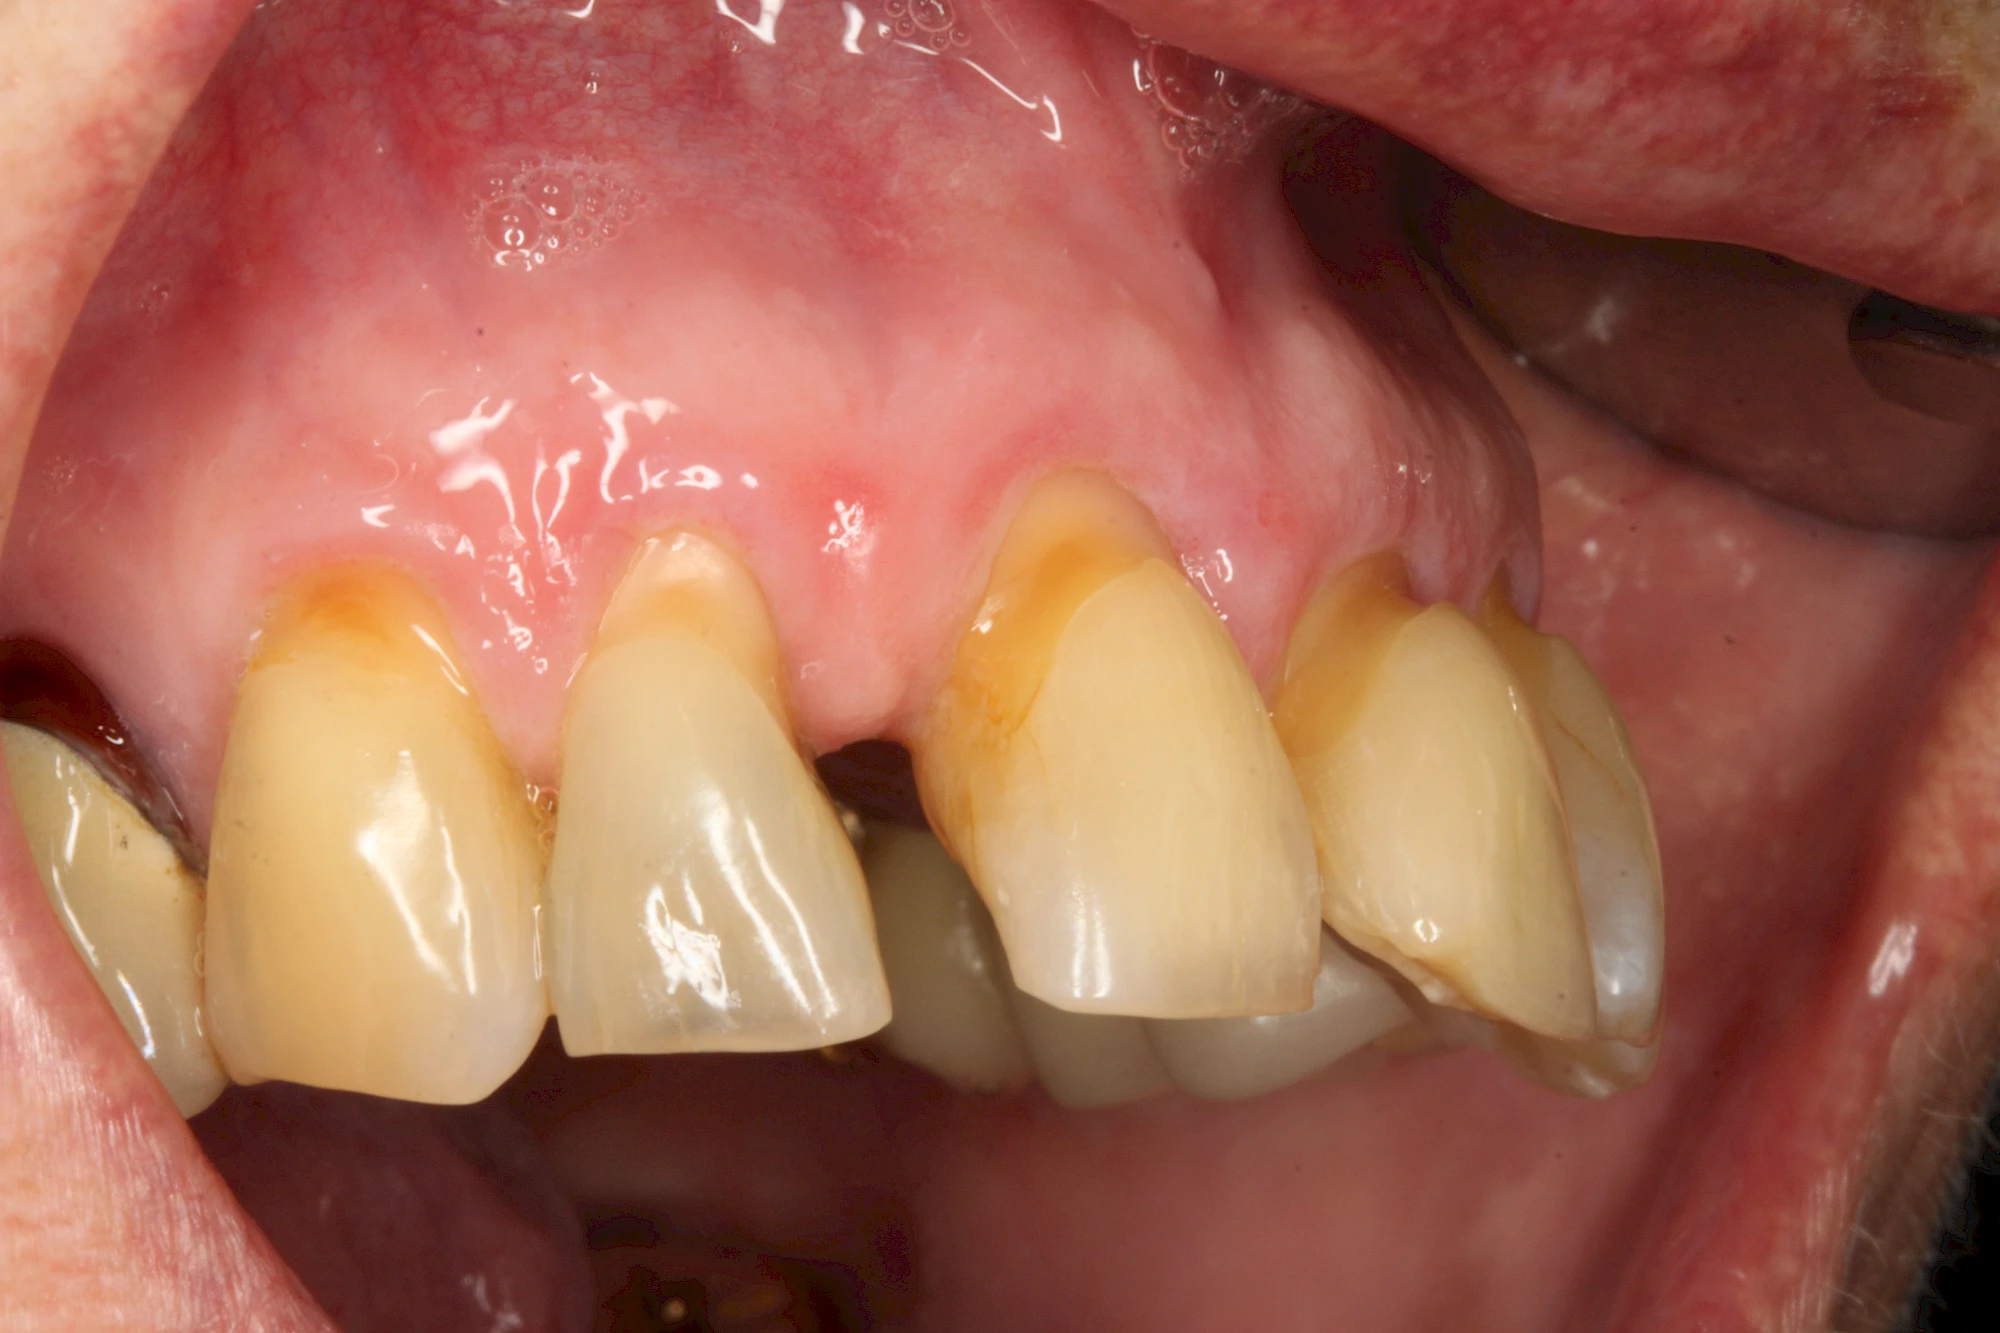

Auswaschung (Erosion) dagegen ist eine Verschleißerscheinung der Zähne aufgrund von immer wiederkehrenden Säureangriffen durch die Nahrung, verstärkt zum Beispiel durch den Genuss säurehaltiger Getränke oder Speisen. Auch bei Menschen mit einer Essstörung (z. B. Bulimie) können die Zähne durch die Magensäure ausgewaschen erscheinen.

Eine Sonderform sind sogenannte keilförmige Defekte im Bereich der Zahnhälse. Hier geht man davon aus, dass Knirschen und Pressen in Kombination mit falschen Putzgewohnheiten (zu hoher Putzdruck, Verwendung von Zahnpasta mit hohen Abrasionswerten) eine Rolle spielen.